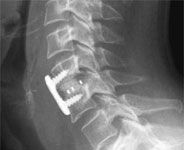

Anterior Cervical Discectomy and Fusion